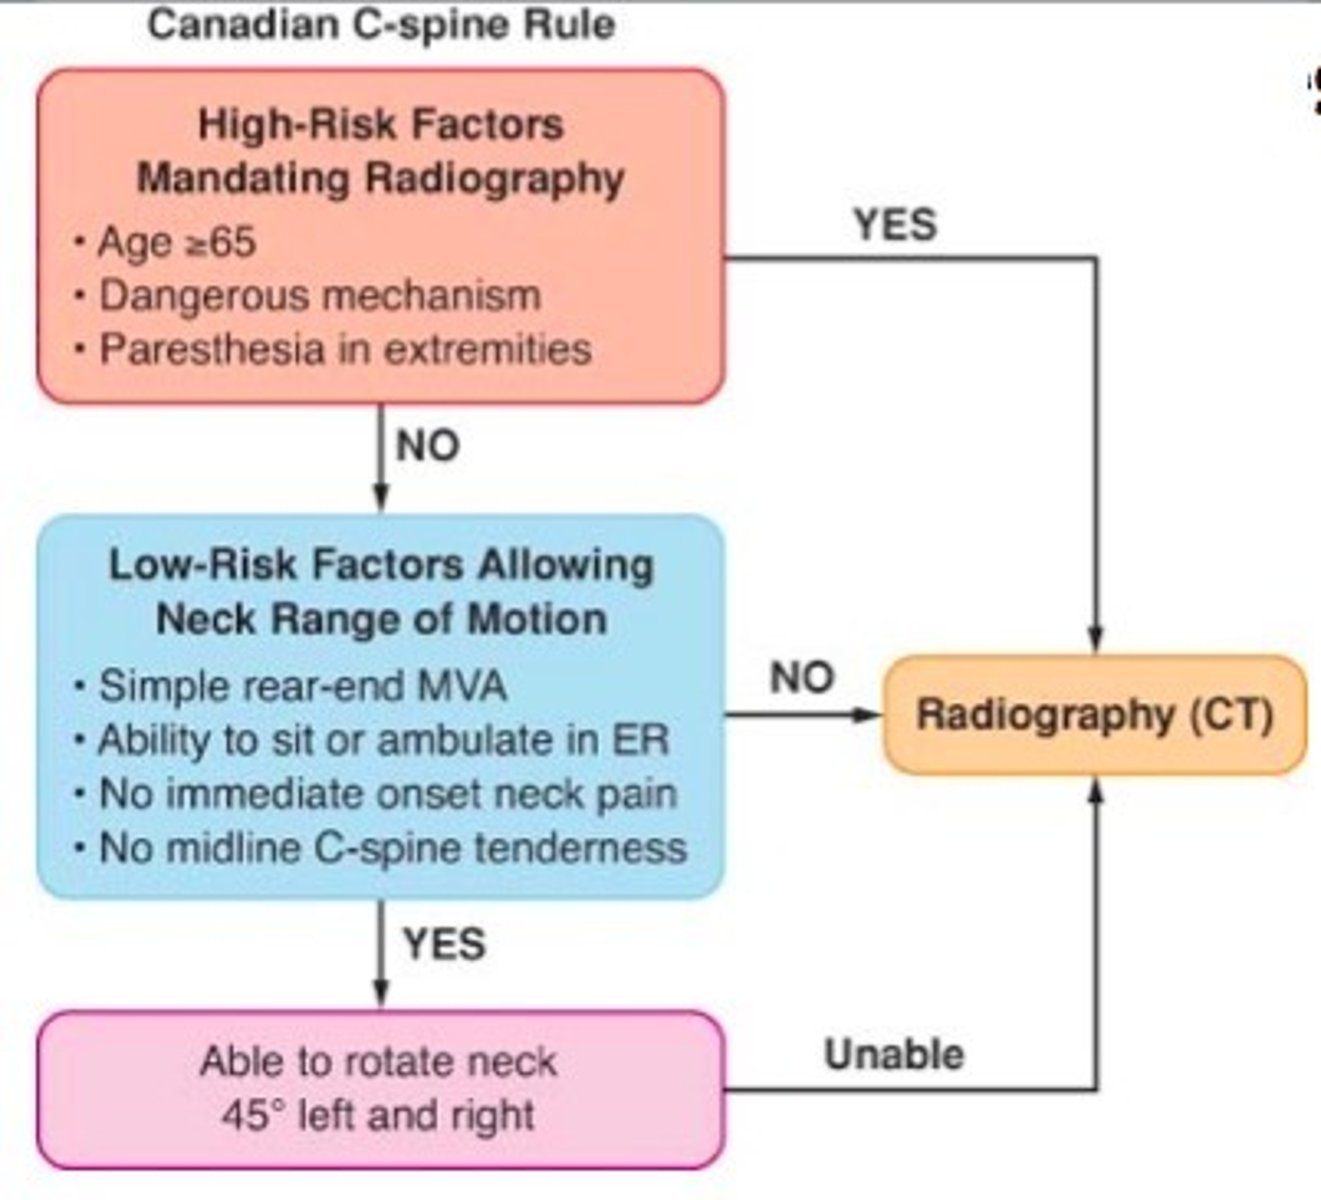

canadian C-spine rule

safely rule out cervical spine injury (CSI) in alert, stable trauma patients without the need to obtain radiographic images, more sensitive and specific than NEXUS, CT usually performed

cervical spine imaging

immobilize neck with C-collar

xray- lateral, spinal fracture/subluxation

CT- usually performed rather than xray, fractures